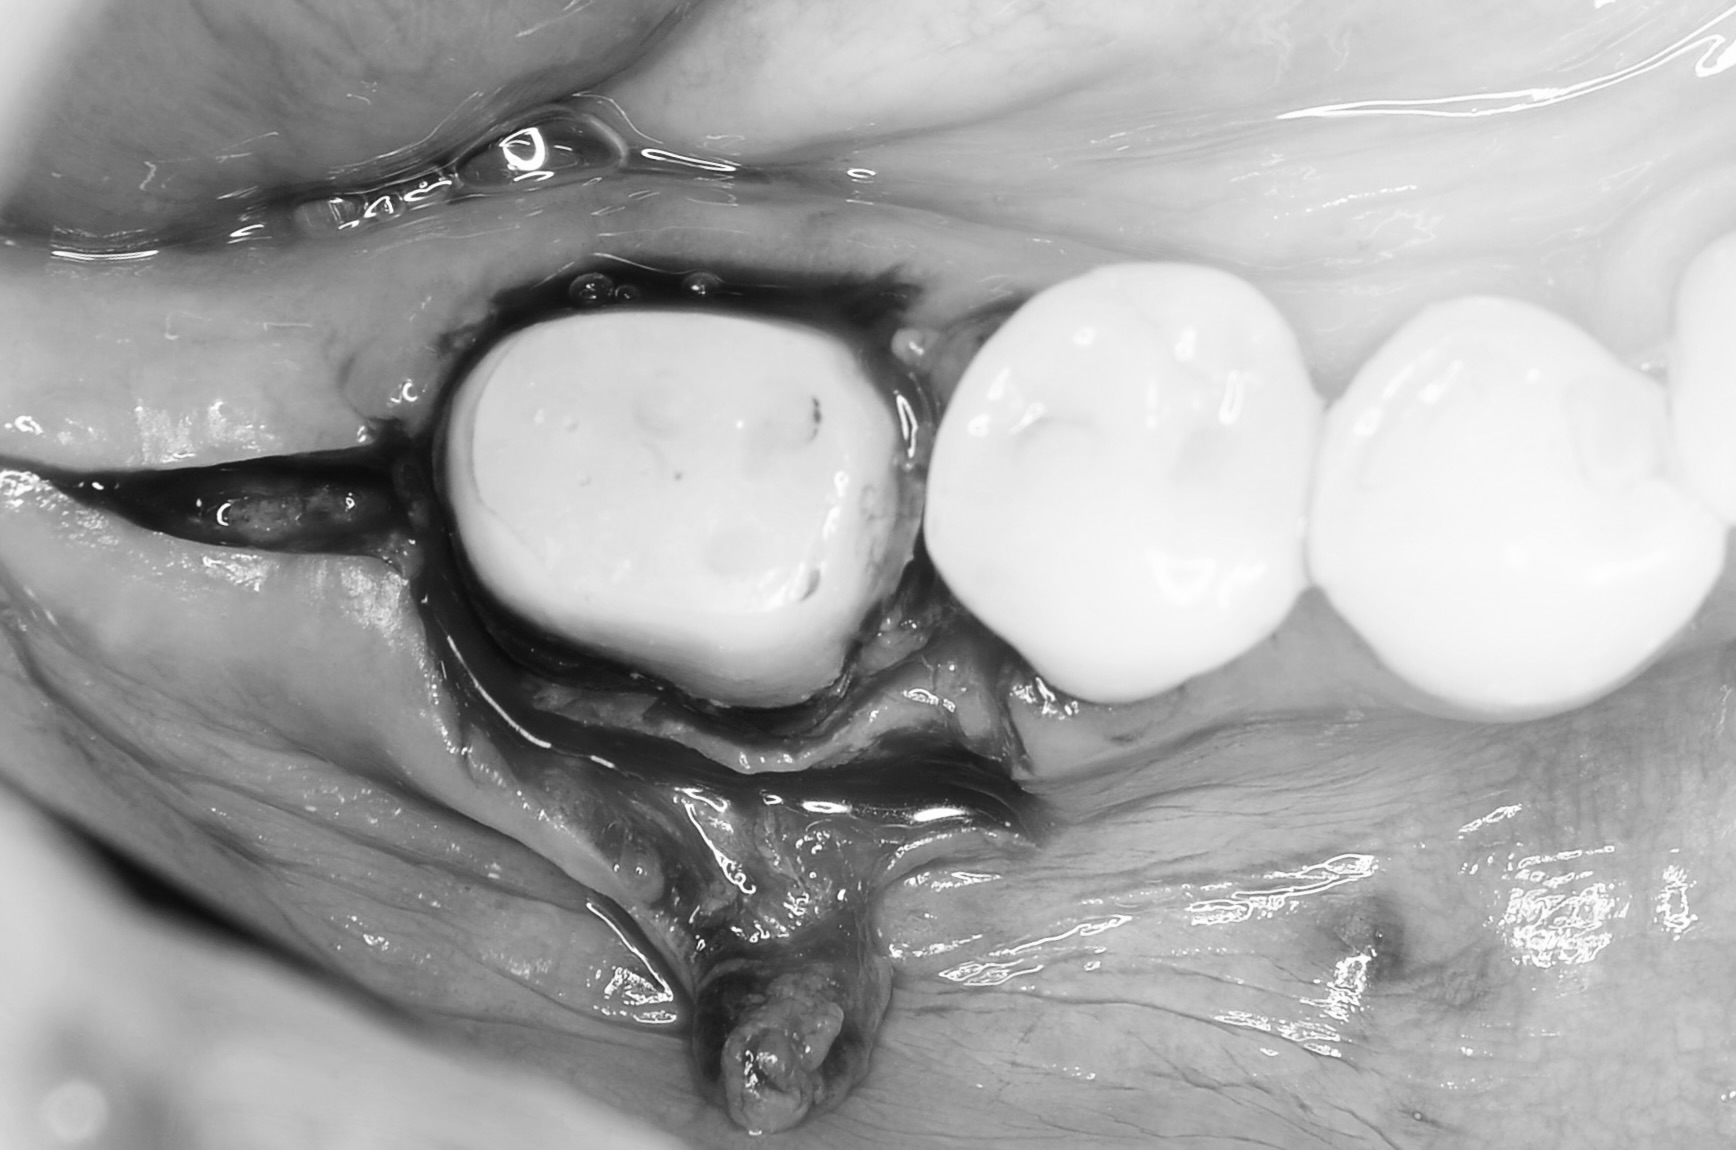

骨外科処置

-

隣在歯との骨の高さのバランスを見ながら歯槽骨を削り歯根を露出させます。 -